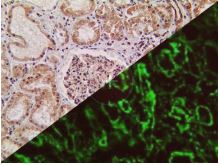

Bio SB has developed a highly sensitive Immunofluorescence and non-biotin monovalent Fab micropolymer IHC detection systems for the detection of IVD antibodies for Complement (C1q, C3c, C3d, C4c, C4d), Serum Proteins (Albumin and Fibrinogen) and Immunoglobulins (IgA, IgD, IgE, IgG, IgM, Kappa and Lambda) related to autoimmune conditions. Our innovative IF and IHC detection systems and high affinity antibodies, have opened the doors for a faster and accurate Immunofluorescence and Immunohistochemistry applicable to Autoimmune Disease like Nephropathies and Lupus.

These antibodies and detection systems are intended for use in Immunohistochemical (IHC) and Immunofluorescence (IF) applications of formalin-fixed paraffin-embedded tissues (FFPE), frozen tissue sections and cell preparations.

Rabbit FluoroDetector FITC |

Rabbit FluoroDetector FITC with FluoroMounter |

Rabbit FluoroDetector FITC with FluoroMounter with DAPI |